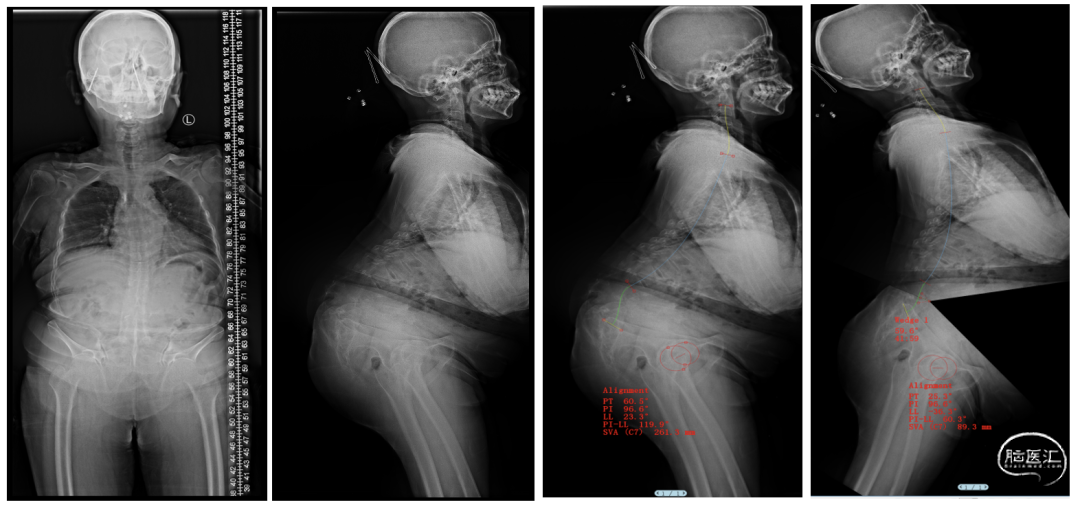

术前影像学检查

脊柱全长片

手术前后对比